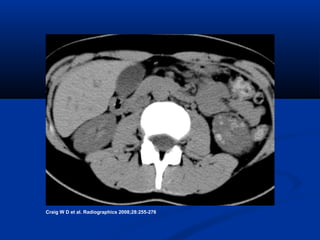

Severe unilateral acute bacterial pyelonephritis

Craig W D et al. Radiographics 2008;28:255-276

• #8 Figure 4a.  Severe unilateral acute bacterial pyelonephritis. (a) US image demonstrates a slightly enlarged right kidney that is otherwise unremarkable, belying the advanced disease. (b) CT scan shows the enlarged kidney with global decreased uptake of contrast material and multiple small low-attenuation foci from abscess pockets, findings that prompted nephrectomy. (c) Photograph of the resected gross specimen reveals multiple intrarenal abscesses that have begun to partially coalesce. Scale is in centimeters.